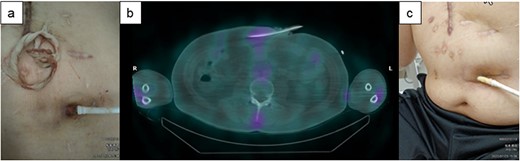

A 60-y-old man with ischemic cardiomyopathy underwent LVAD implantation (HeartMate II™, Abbott Co., Abbott Park, IL, USA) 2 y before being admitted to our hospital because of pain and skin redness above the umbilicus. He had no skin induration and tenderness at the DLES; however, redness, local increase in temperature, and skin induration and tenderness were noted above the umbilicus (Fig. 3a). As the inflammatory area was far from the DLES, surgical debridement and associated relocation of the exit site were considered. 67Ga SPECT showed a high signal up to 5 cm inside the DLES (Fig. 3b). The empirical antibiotics were administered intravenously after collection of cultures of exit site and drained fluid. First, the catheter cleaning method via the DLES was executed, daily bedside debridement with 10% silver nitrate solution was performed via the DLES to eliminate the contaminated tissue for about 1 week. In this patient, the DLES and spot with redness were distant, and it was suspected that the infected granulation tissue affected the discharge of the exuded solution. Therefore, monofilament nylon threads were inserted for continuous drainage (Fig. 3a). Simultaneously, daily irrigation using an intravenous indwelling catheter was continued with a 1000-ml saline solution for about 1.5 months (Fig. 2e). Although repeated culture of drained fluid did not detect the definitive pathogenic bacterium, intravenous antibiotics were used for about 6 weeks but were then switched to oral antibiotics. The spot with redness healed, and the patient was discharged from the hospital 2 months after admission (Fig. 3c). This patient was readmitted for a similar DLI 4 months later and was treated with the same catheter method for about 3 weeks. Then, DLI did not reoccur until 1.5 y later.

The clinical course of development of the DLI in Case 1. (a) There was some distance between the DLES and the spot with redness and induration. (b) 67Ga SPECT shows high signalization within reach of the cotton swab and intravenous catheter from DLES. (c) The spot with redness and induration healed after treatment with this catheter method.